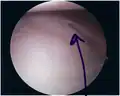

Bankart lesion

The glenoid labrum, labeled glenoid ligament, is damaged in a Bankart lesion. Lateral view demonstrating the articular surface of the right scapula is shown.

The diagnosis is usually initially made by a combination of physical exam and medical imaging, where the latter may be projectional radiography (in cases of bony Bankart) and/or MRI of the shoulder. The presence of intra-articular contrast allows for better evaluation of the glenoid labrum.[8] Type V SLAP tears extends into the Bankart defect.[9]